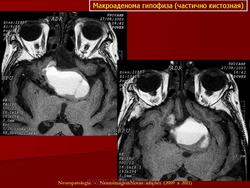

Кистозная аденома.

Приложения:

21.kistoznaya_adenoma_gipofiza.jpg22.kistoznaya_adenoma_gipofiza.jpg